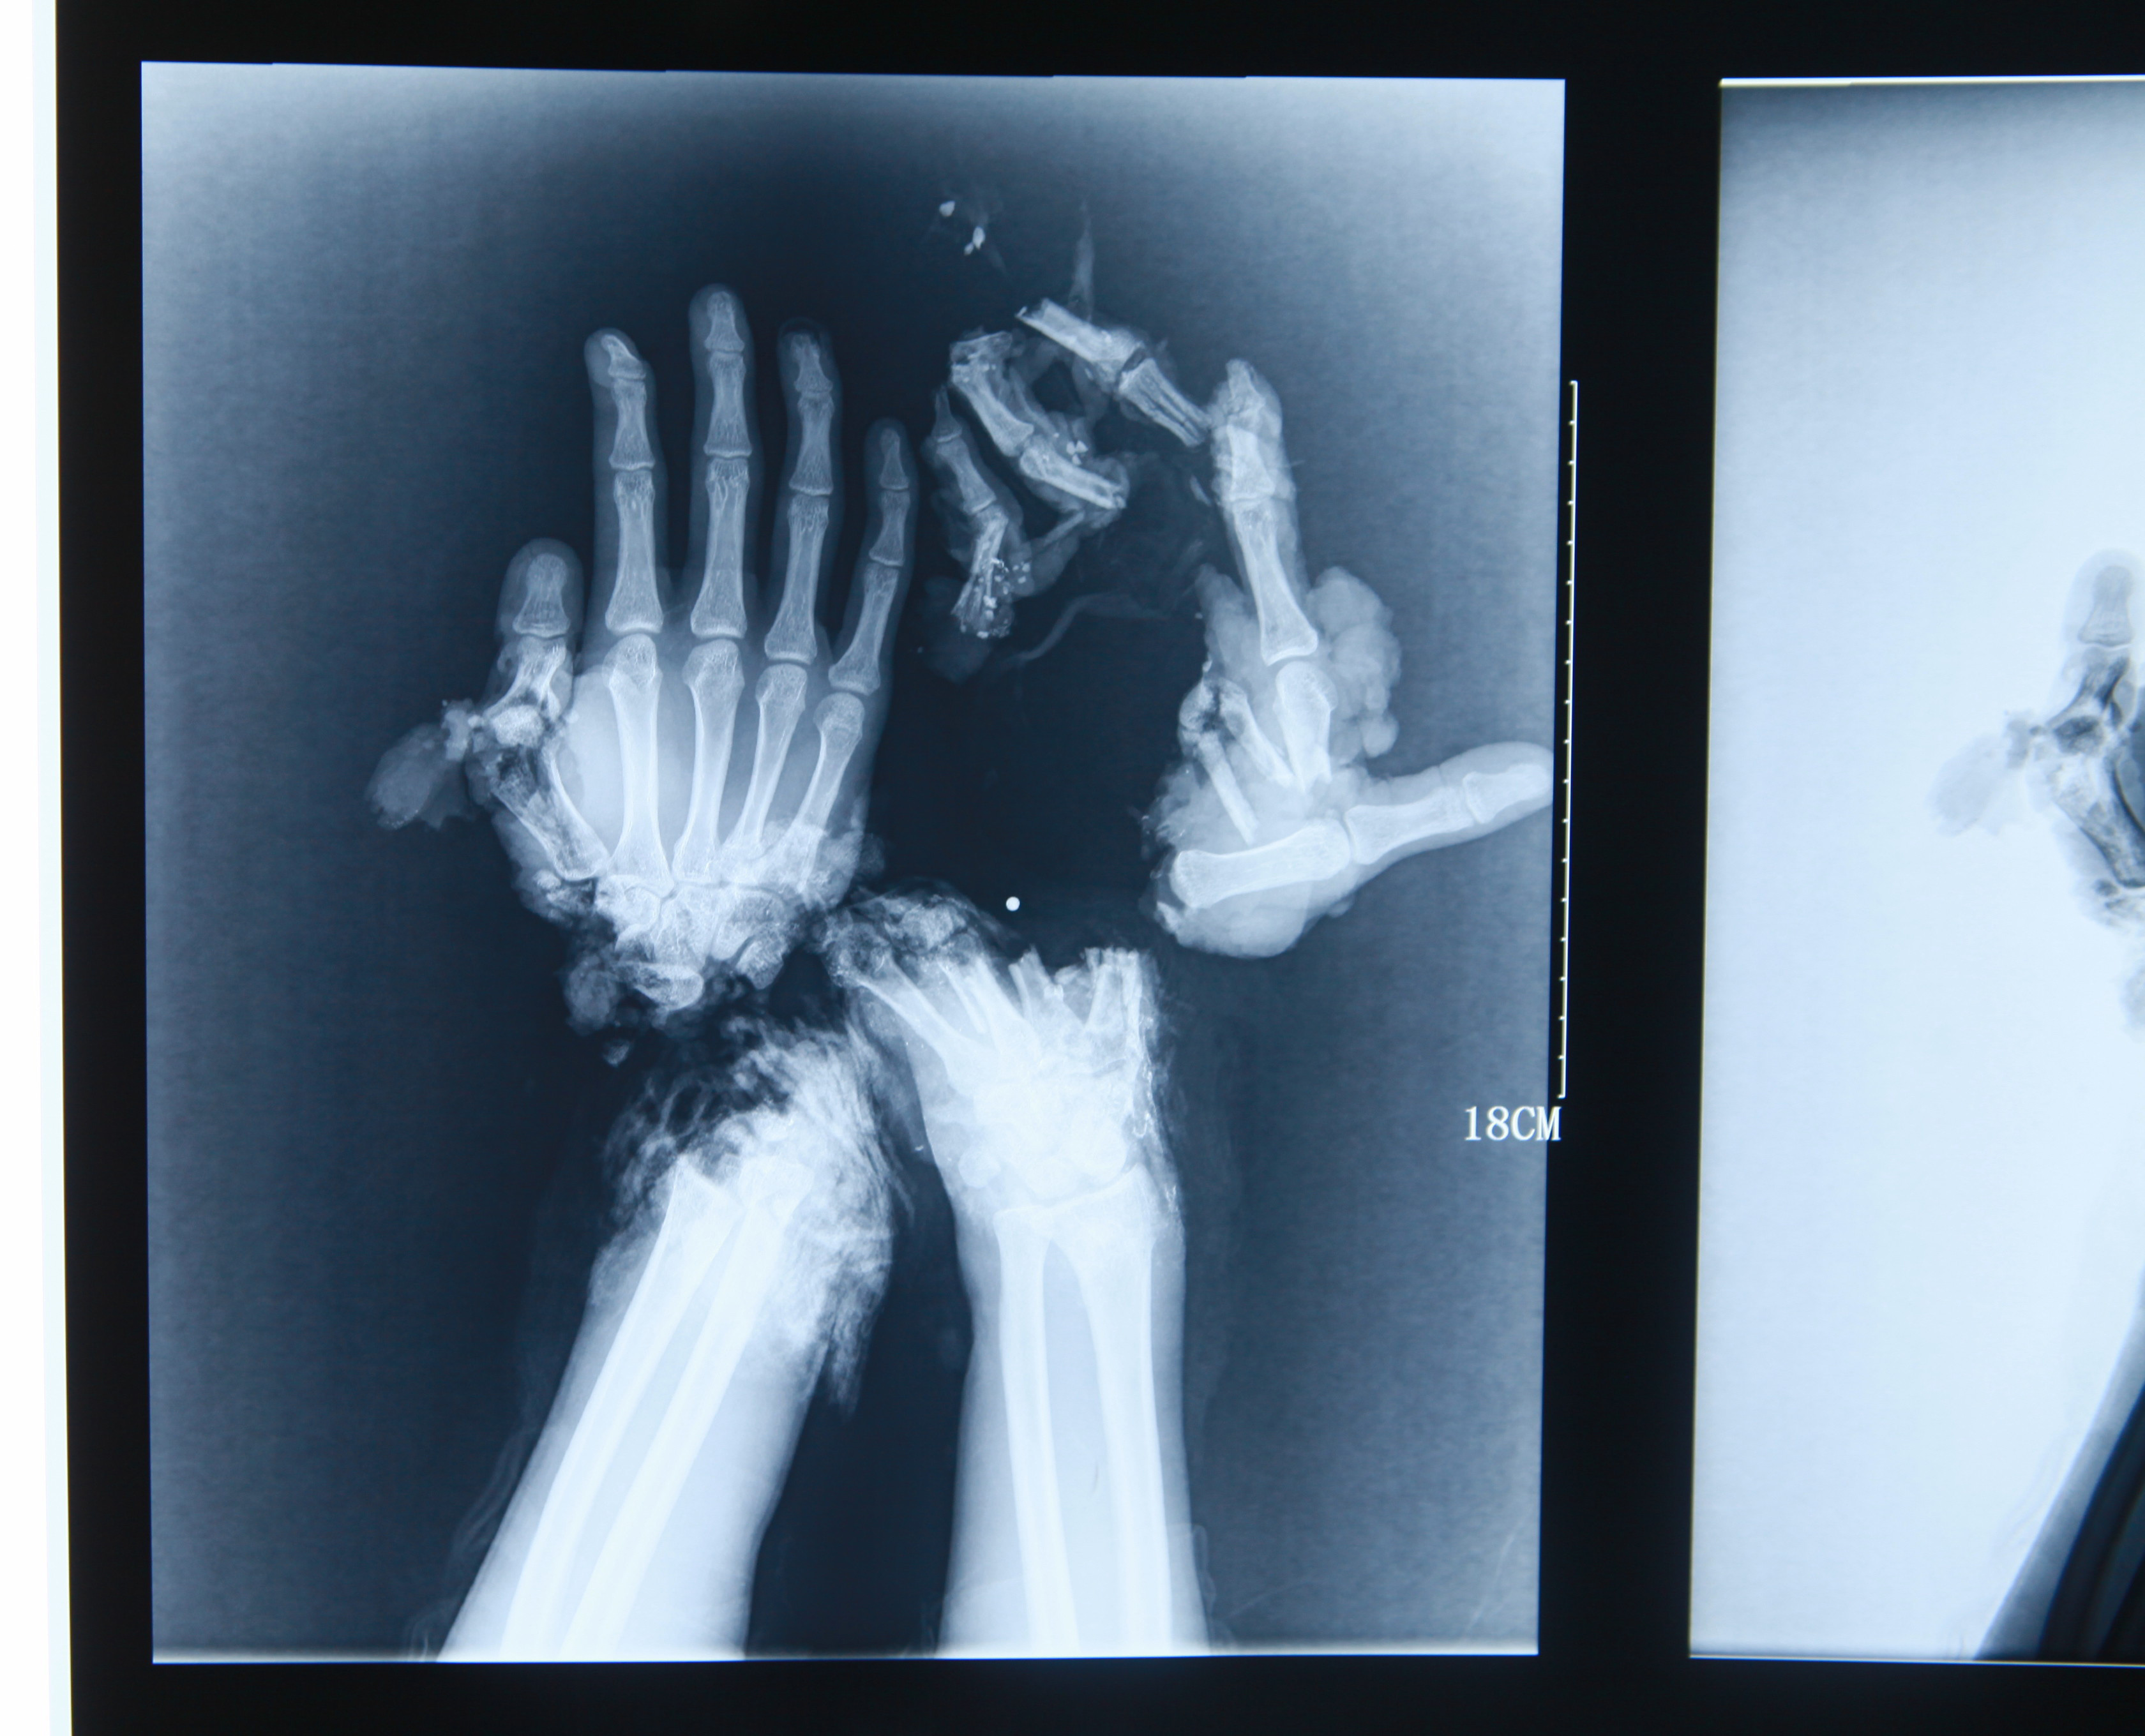

A broken hand x-ray is a diagnostic imaging test that uses radiation to create images of the bones in the hand. This imaging technique is essential for identifying fractures and assessing the severity of an injury. X-rays can reveal various types of injuries, ranging from hairline fractures to complete breaks.

X-rays work by passing a small amount of radiation through the body. Dense structures like bones absorb more radiation than softer tissues, resulting in a contrast that allows the bones to appear white on the x-ray film. This contrast is what makes x-rays effective for diagnosing fractures.

Interpreting the results of a broken hand x-ray requires expertise and knowledge of anatomy. Here are some key aspects to consider:

- Fracture Lines: The presence of fracture lines indicates a break in the bone.

- Alignment: The alignment of the bones is crucial. Misaligned fractures may require surgical intervention.

- Bone Density: Changes in bone density can indicate underlying conditions such as osteoporosis.

Types of Hand Fractures

There are several types of fractures that can occur in the hand, including:

- Distal Radius Fracture: A common fracture that occurs near the wrist.

- Metacarpal Fracture: A fracture of the long bones in the hand, typically occurring due to a punch.

- Phalanx Fracture: Fractures of the finger bones, which can be particularly painful.